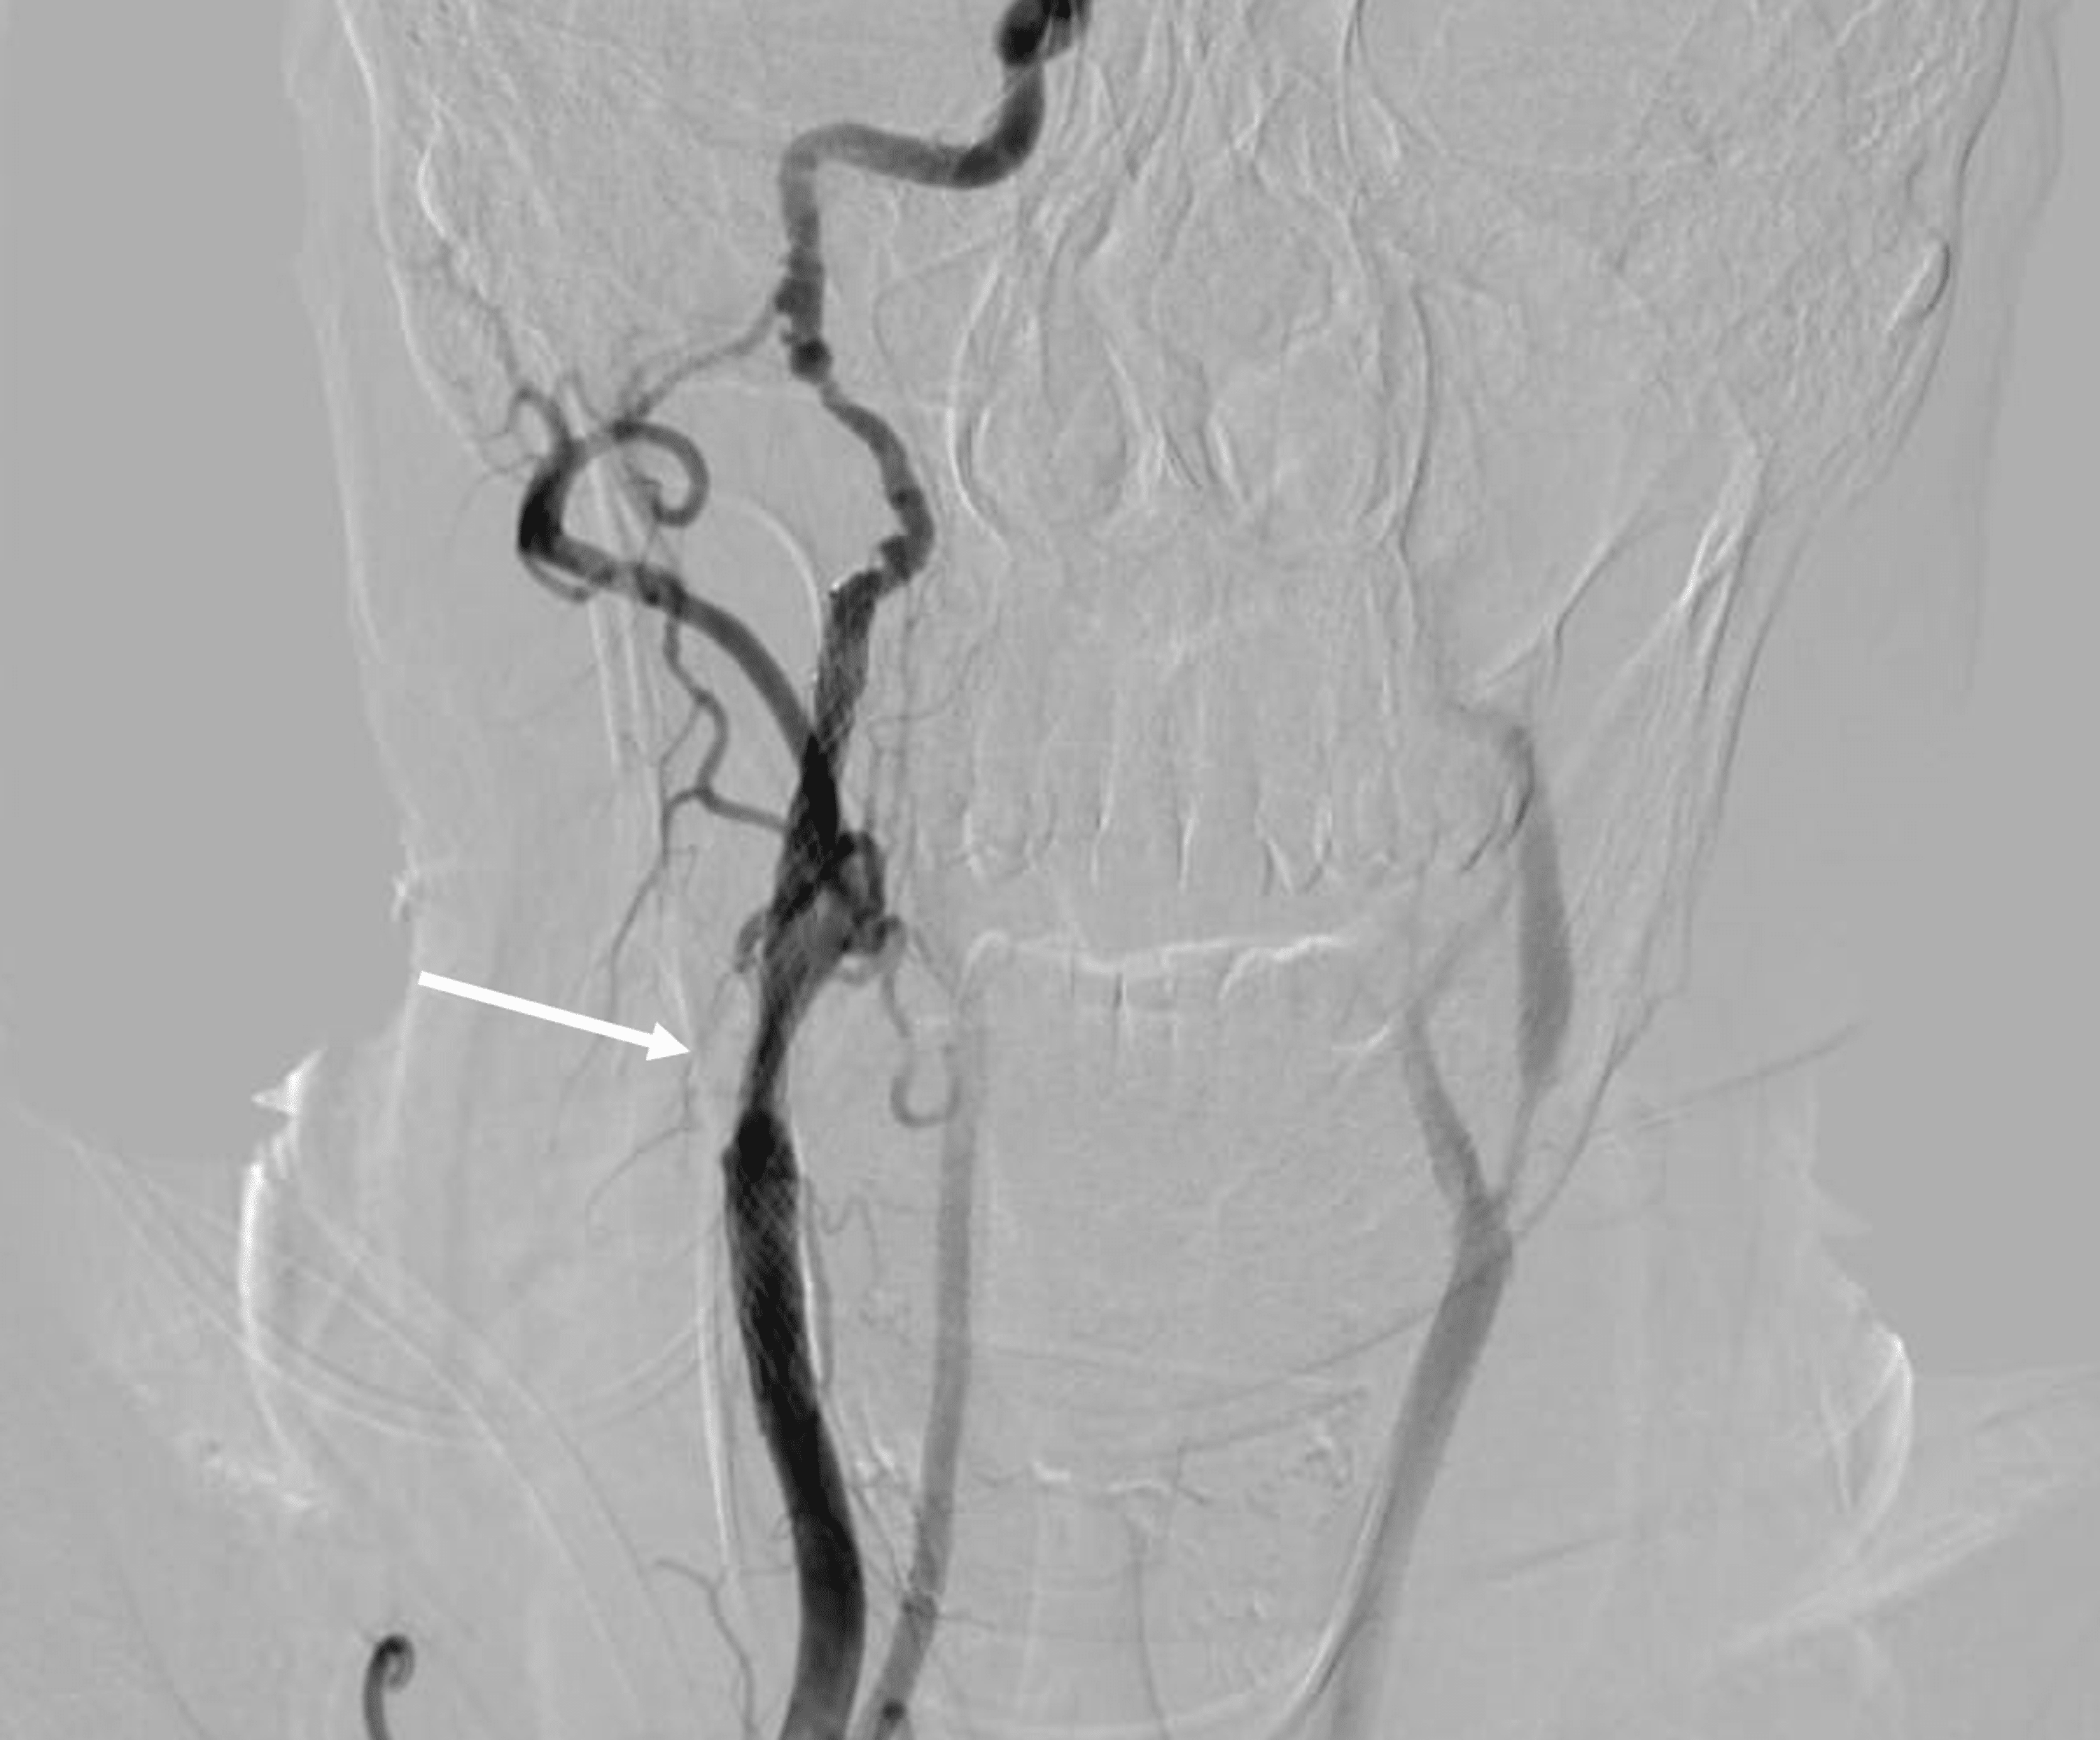

From www.cureus.com

Hand Knob Syndrome Secondary to Ipsilateral Carotid Fibromuscular Dysplasia and What Is A Hand Knob Stroke — clinical manifestation: — hand knob stroke is a rare stroke with a good prognosis and a low stroke recurrence rate. Left hand weakness and sensory deficit. This anatomic landmark is responsible for intricate control of hand motor movements and has often been implicated in motor weakness following stroke. — cortical ischemic stroke affecting the precentral “hand. What Is A Hand Knob Stroke.